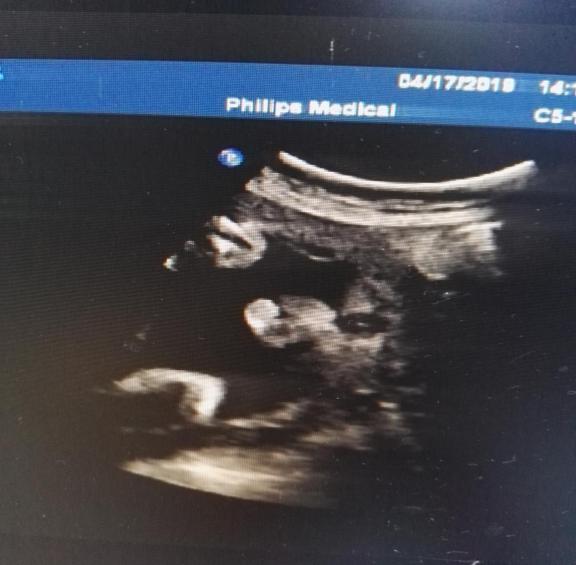

F2胎儿超声测值:

双顶径 75mm,头围 289mm,腹围243mm,股骨长 54mm,最大羊水深度 53mm,羊水内见一条带样高回声漂浮。

胎心率 156次/分,胎盘位于后壁,厚约31mm。

阳性指征:探查时胎儿外生殖器呈“郁金香”征。

超声提示:胎儿外生殖器呈“郁金香”征(待排),建议复查